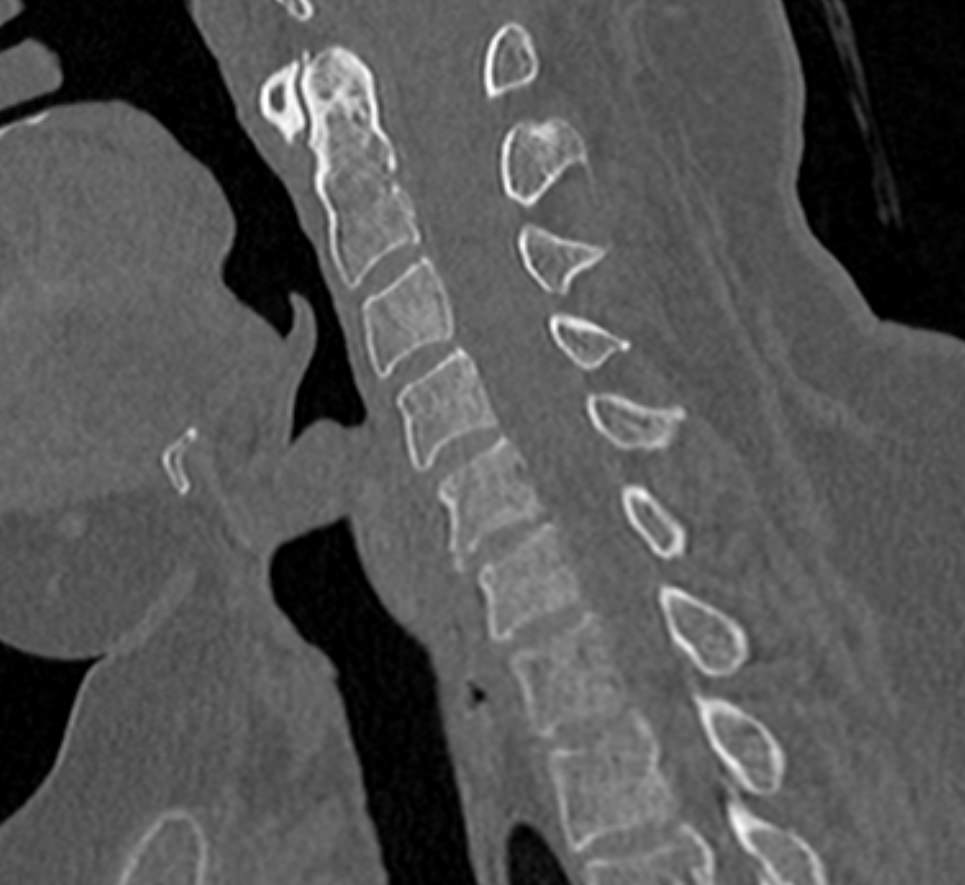

Мультиспиральная компьютерная томография является одним из наиболее информативных методов диагностики дегенеративно-дистрофических заболеваний, травматических, воспалительных изменений, а также опухолевых процессов позвоночника. Методика предусматривает использование рентгеновского излучения для получения детализированных снимков костных структур позвоночника, межпозвонковых суставов и межпозвоночных дисков.

При подозрении на распространенный процесс с поражением различных уровней позвоночного столба показано проведение мультиспиральной КТ трех отделов позвоночника.

В клинике «Доступная медицина» установлены современные мультиспиральные компьютерные томографы экспертного класса TOSHIBA AQUILION в различных модификациях (64-срезовый и 128-срезовый), на которых выполняются комплексные обследования позвоночника, включая одномоментное исследование несколько отделов. Аппараты производят сканирование с помощью рентгеновских лучей, делая тончайшие срезы с шагом от 0,5 мм, затем с помощью компьютерных программ полученные данные преобразуются в изображения трехмерного формата, что обеспечивает точность и достоверность диагностики.

С помощью мультиспиральной КТ можно диагностировать:

- дегенеративно-дистрофические заболевания позвоночника (остеоартроз, спондилез, деформирующий спондилоартроз);

- травматические повреждения позвоночника (компрессионные и оскольчатые переломы);

- стеноз (сужение) позвоночного канала;

- грыжи межпозвонковых дисков (протрузии, экструзии и грыжи Шморля);

- спондилиты, гнойные артриты, сакроилеит, абсцессы околопозвоночных тканей и другие воспалительные заболевания, туберкулез;

- хронические системные заболевания позвоночника (болезнь Бехтерева);

- опухоли позвоночника и окружающих тканей;

- патологические изгибы позвоночника, сколиоз, усиленный или выпрямленный лордоз как нарушение статической функции позвоночника;

- аномалии строения позвоночника.